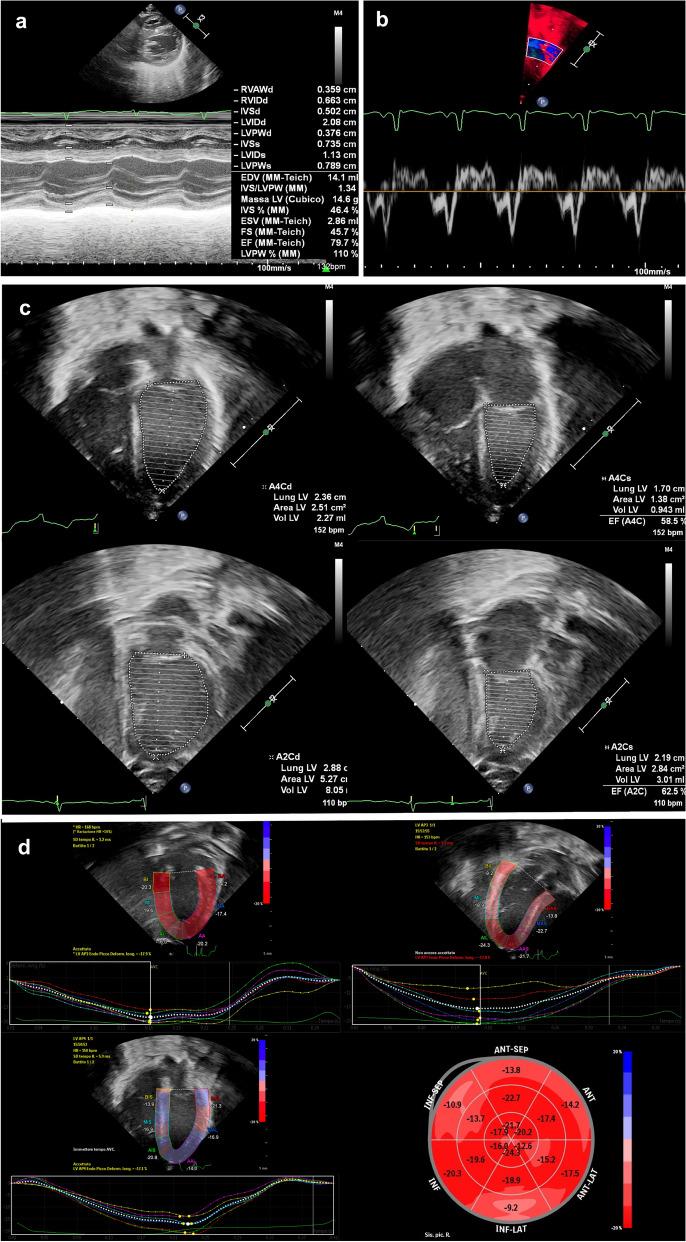

Echocardiographic assessment of left ventricular function is crucial in NICU. The study aimed to compare the accuracy and agreement of global longitudinal strain (GLS) with conventional measurements. Real-life echocardiograms of neonates receiving intensive care were retrospectively reviewed. Shortening fraction (SF), ejection fraction (EF) and S' measurements were retrieved from health records. GLS was calculated offline from stored images. The association with stroke volume indexed for body weight (iSV) was evaluated by regression analysis. The diagnostic ability to identify uncompensated shock was assessed by ROC curve analysis. Cohen's κ was run to assess agreement. 334 echocardiograms of 155 neonates were evaluated. Mean ± SD gestational age and birth weight were 34.5 ± 4.1 weeks and 2264 ± 914 g, respectively. SF, EF, S' and GLS were associated with iSV with R of 0.133, 0.332, 0.252 and 0.633, (all p < .001). Including all variables in a regression model, iSV prediction showed an adjusted R of 0.667, (p < .001). GLS explained 73% of the model variance. GLS showed a better ability to diagnose uncompensated shock (AUC 0.956) compared to EF, S' and SF (AUC 0.757, 0.737 and 0.606, respectively). GLS showed a moderate agreement with EF (κ = .500, p < .001) and a limited agreement with S' and SF (κ = .260, p < .001, κ = .242, p < .001). GLS was a more informative index of left ventricular performance, providing the rationale for a more extensive use of GLS at the cotside.

新生儿重症监护病房(NICU)中左心室功能的超声心动图评估至关重要。本研究旨在比较整体纵向应变(GLS)与传统测量方法的准确性和一致性。回顾性分析接受强化治疗的新生儿的实时超声心动图。从健康记录中检索缩短分数(SF)、射血分数(EF)和 S'测量值。从存储的图像中离线计算 GLS。通过回归分析评估与体重指数(iSV)的相关性。通过 ROC 曲线分析评估识别代偿性休克的诊断能力。使用 Cohen's κ 评估一致性。共评估了 155 例新生儿的 334 次超声心动图。平均(±SD)胎龄和出生体重分别为 34.5(±4.1)周和 2264(±914)g。SF、EF、S'和 GLS 与 iSV 相关,R 值分别为 0.133、0.332、0.252 和 0.633(均 P < 0.001)。在回归模型中包含所有变量时,iSV 预测的调整 R 为 0.667(P < 0.001)。GLS 解释了模型方差的 73%。GLS 诊断代偿性休克的能力优于 EF、S'和 SF(AUC 0.956 比 AUC 0.757、0.737 和 0.606,均 P < 0.001)。GLS 与 EF 具有中等一致性(κ=0.500,P < 0.001),与 S'和 SF 一致性有限(κ=0.260,P < 0.001,κ=0.242,P < 0.001)。GLS 是一种更具信息量的左心室功能指标,为床旁更广泛使用 GLS 提供了依据。